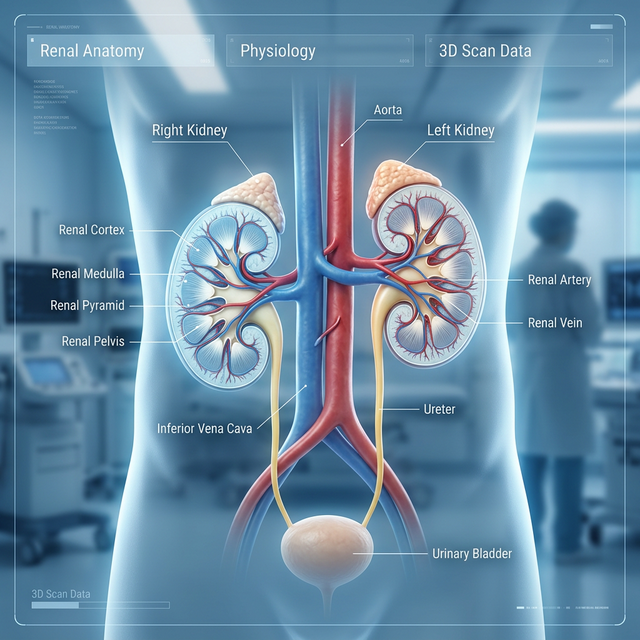

Entenda o que é a TFG, como ela é medida e por que é o principal indicador da saúde renal.